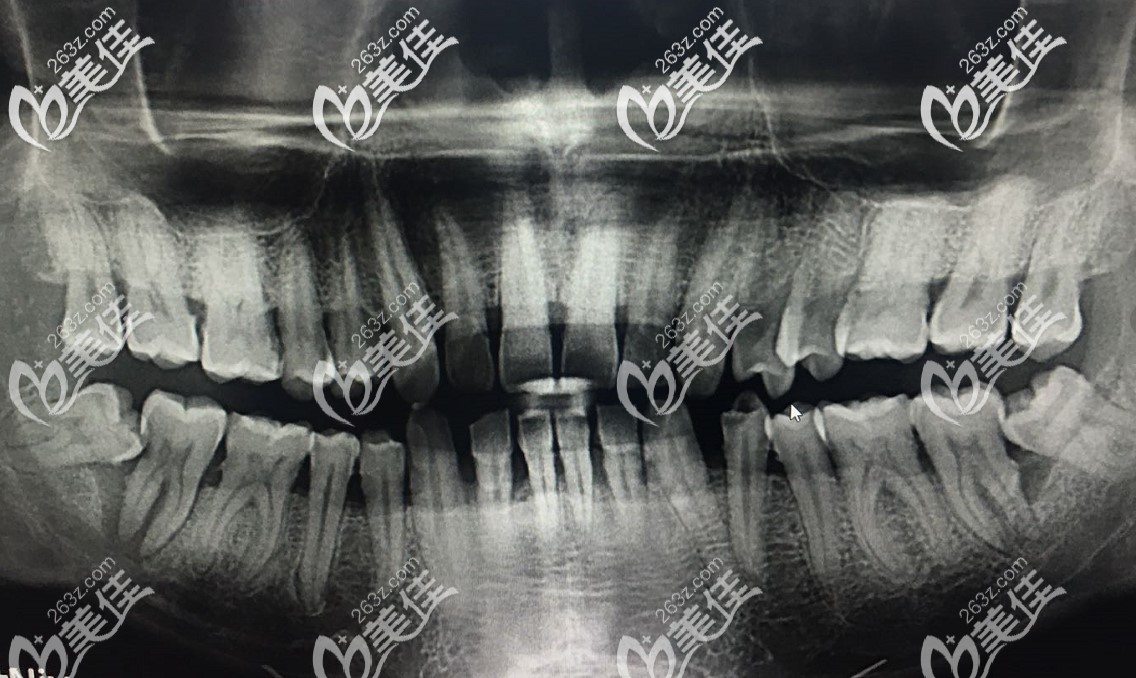

牙齒剛開始疼的時候沒在意,疫情期間在家疼的我坐立難安,好不容易等到口腔醫(yī)院開門,去檢查,醫(yī)生說是橫生智齒導(dǎo)致的,拍片后發(fā)現(xiàn),我的第二磨牙也被智齒頂了個洞。

拔掉智齒之后,醫(yī)生說,我的挨著智齒的那個大牙壞的比較厲害,已經(jīng)傷到了神經(jīng)(自己吃東西的時候,冷了熱了都感覺疼的難受)。并且第二磨牙還松動,如果治療價值不大,建議拔掉做種植牙。

后來又看了其他醫(yī)生,說可以先進(jìn)行根管治療,然后再戴個牙冠,不過具體治療好后,這個牙能用多久,他也不敢保證。